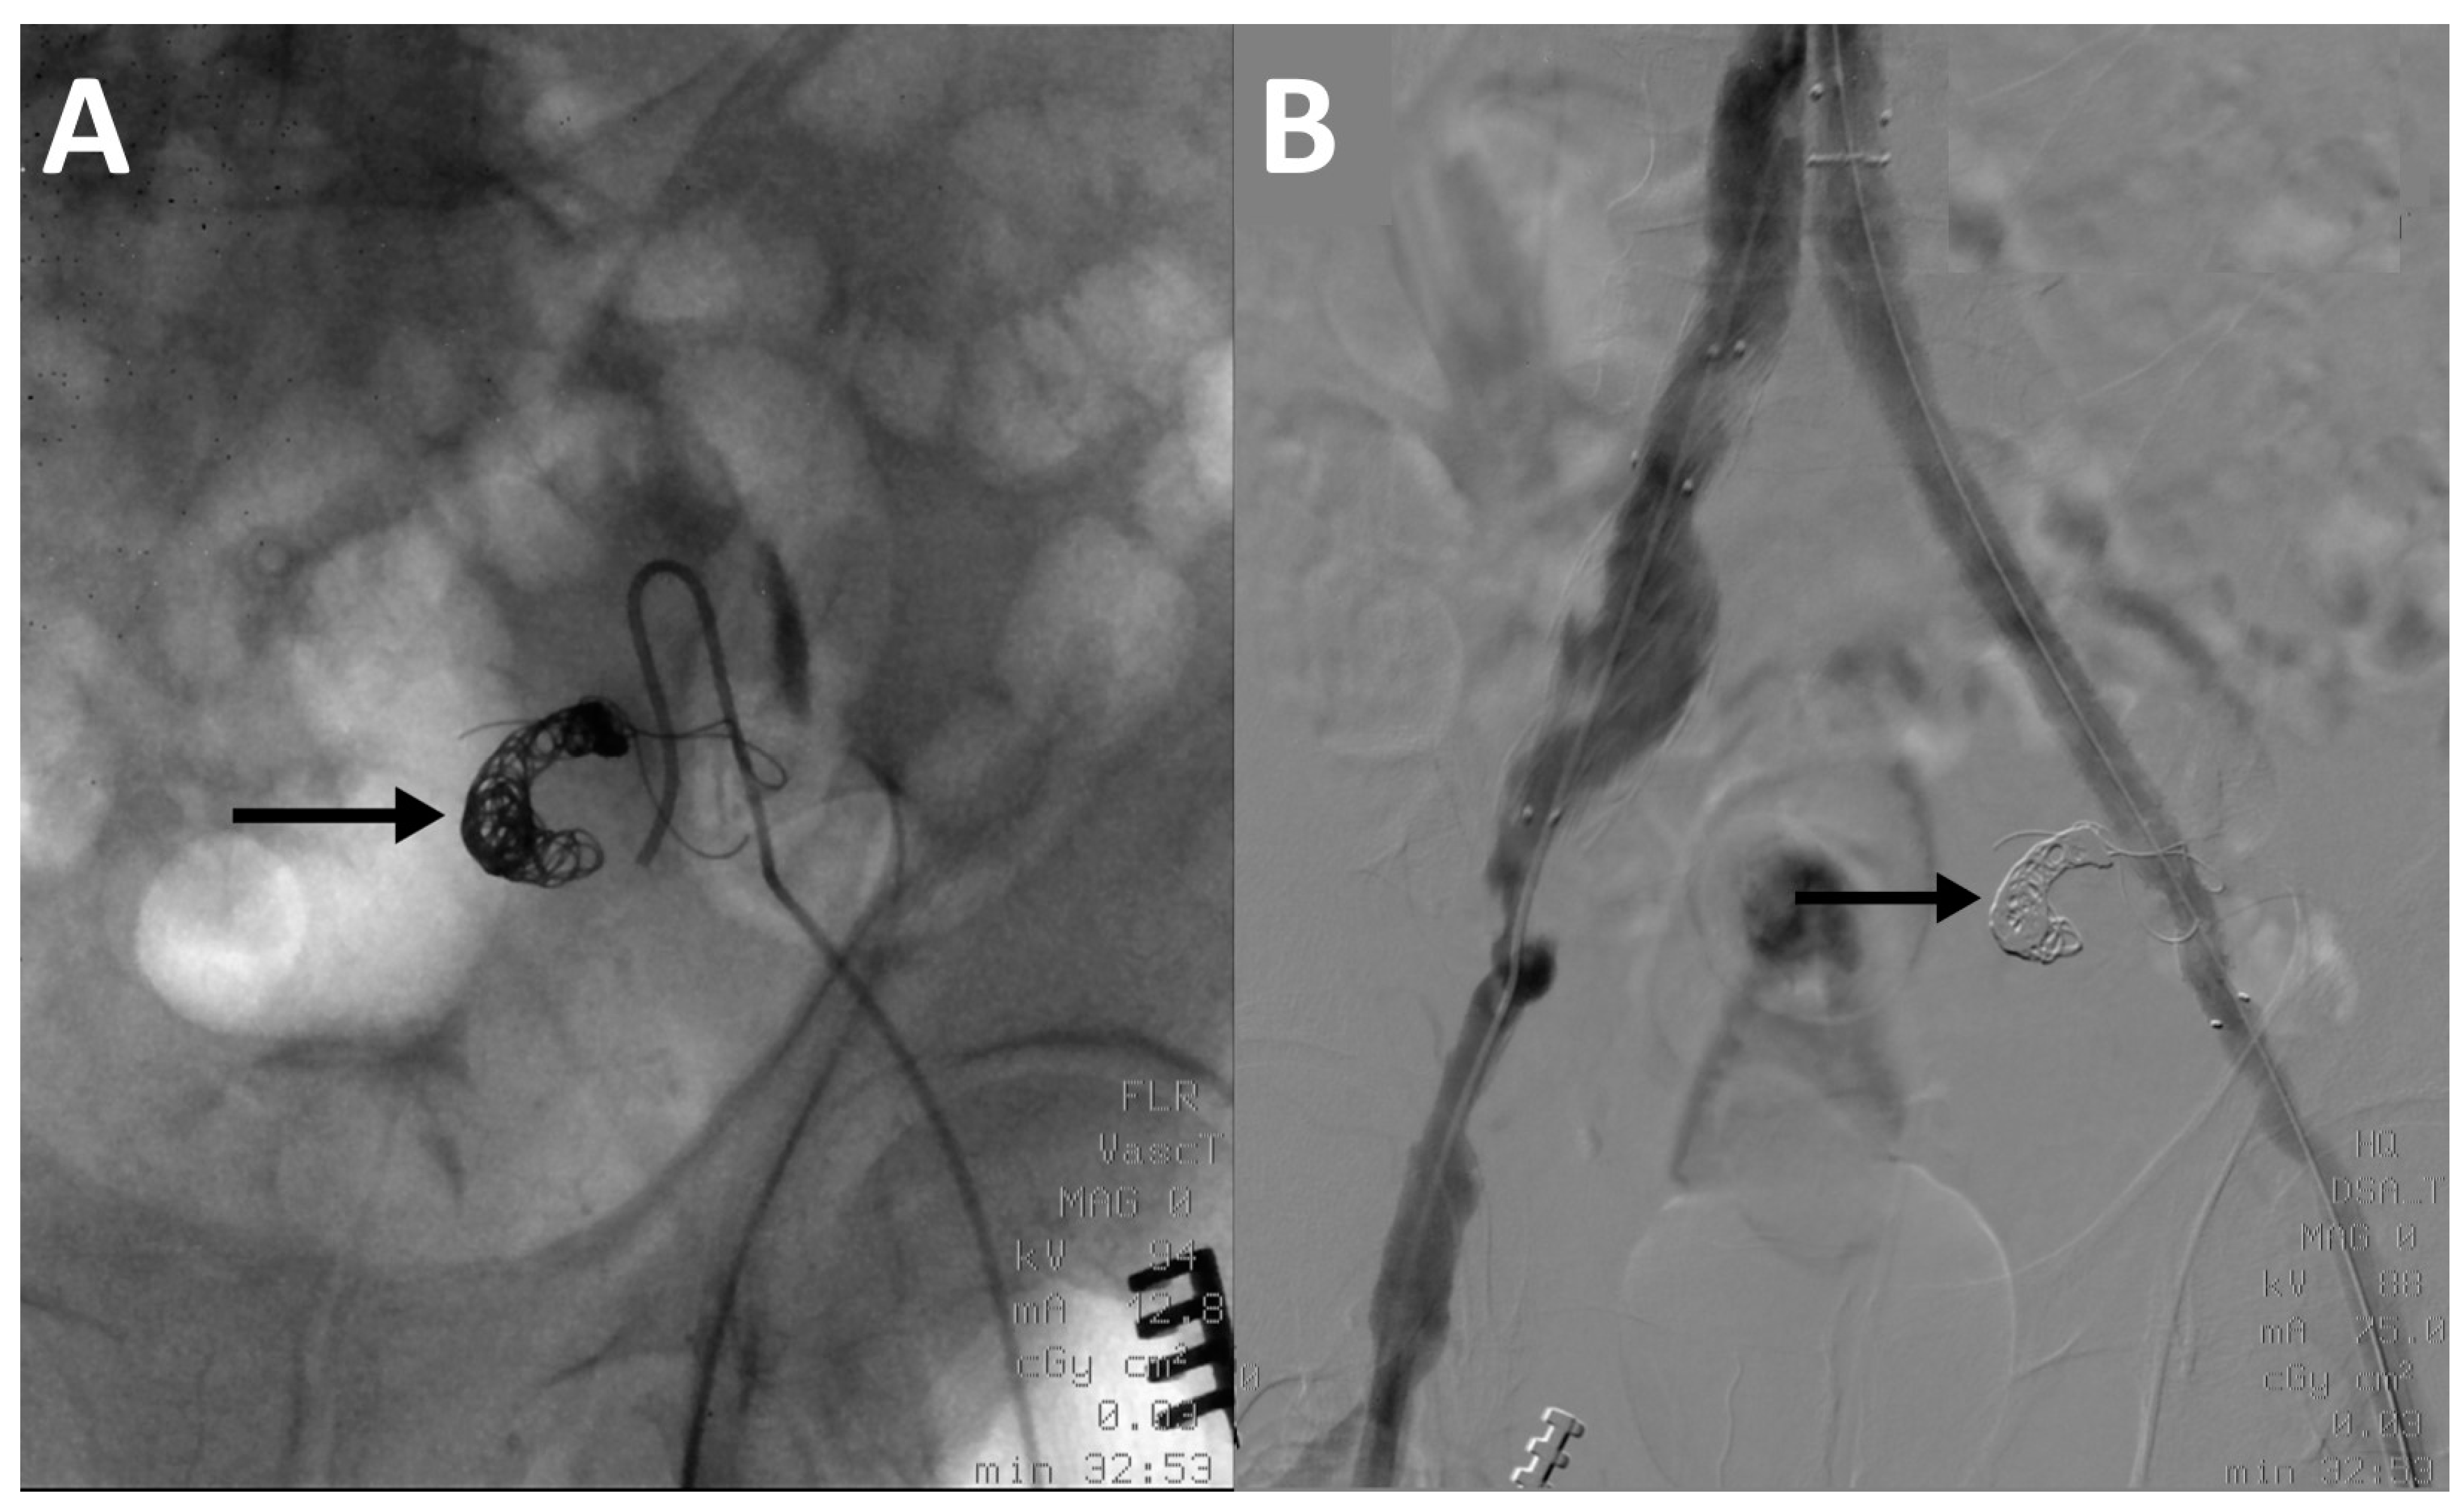

Successful coil embolization of gastroduodenal artery aneurysm. Arrow Coil Embolization Heparin    two factors associated with better outcomes were greater use of endovascular services and a higher percentage of patients transferred from.  for unruptured aneurysm treatment, it is helpful to consider the scenarios of primary coil embolization, coiling with balloon.   the main clinical roles of heparin during endovascular embolization for the treatment of asah are systemic. A procedure, performed. Coil Embolization Heparin.

From www.researchgate.net